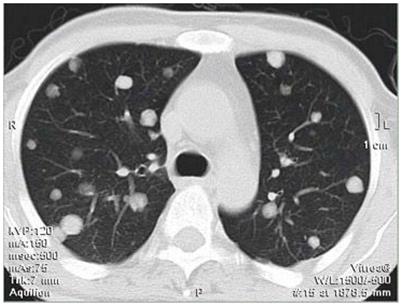

所谓的“转移性肺癌”,指的是全身任何部位的癌症通过血行转移、淋巴转移、直接浸润、气管种植等方式转移到肺部所继发形成的“肺癌”。而通常我们所说的肺癌,都是指原本就发生在肺部的恶性肿瘤。

双肺转移癌

全身很多部位的癌症都可以转移到肺部。最常见的有甲状腺癌、乳腺癌、肾癌、绒毛膜癌、骨肉瘤等,肺部转移发生率为60%~90%;其他较容易转移到肺部的恶性肿瘤包括肺癌(从一个肺叶转移到其他肺叶)、肝癌、胃癌、结直肠癌、前列腺癌等,肺部转移发生率为35%~55%。